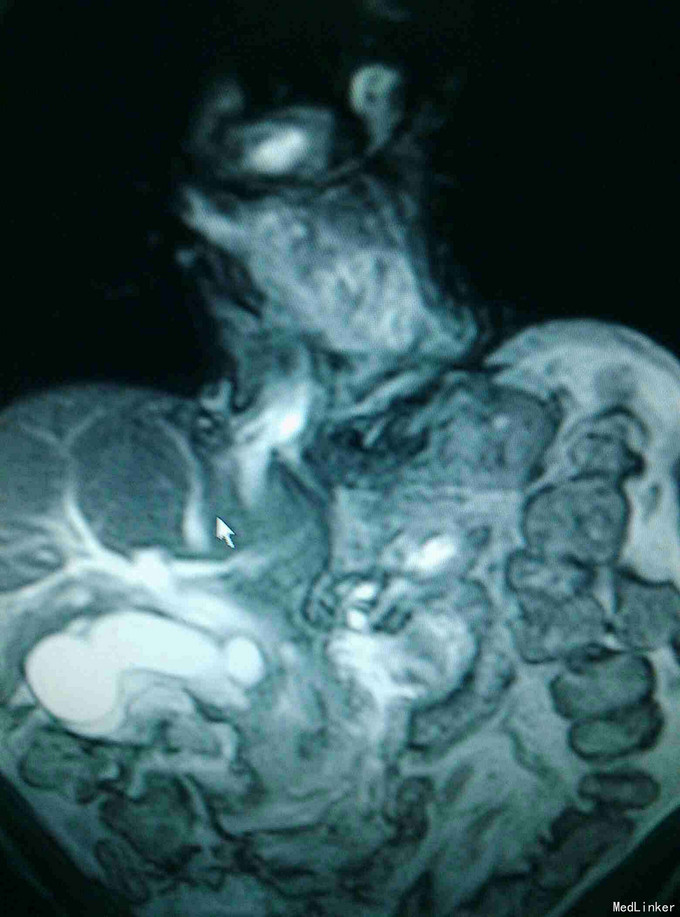

男患,74岁“发现全身皮肤及黏膜黄染2周”,2周前发现皮肤黄染,伴有纳差、厌油,无明显皮肤瘙痒,无发热、寒战,无恶心、呕吐,大便稍稀,无明显白陶土样大便,小便颜色基本正常。

全身皮肤黄染,虹膜黄染,心肺未见异常,腹部稍膨隆,肝区轻度扣击痛,Murphy症阴性。腹部查体腹部B超提示:肝内外胆管扩张,胆囊结石,胆总管下端可见低回声团。MRI如下:

梗阻性黄疸,择日进行了“胆囊切除,胆肠吻合术”,术中见胆囊及上段胆总管明显扩张,下段胆总管塌陷。